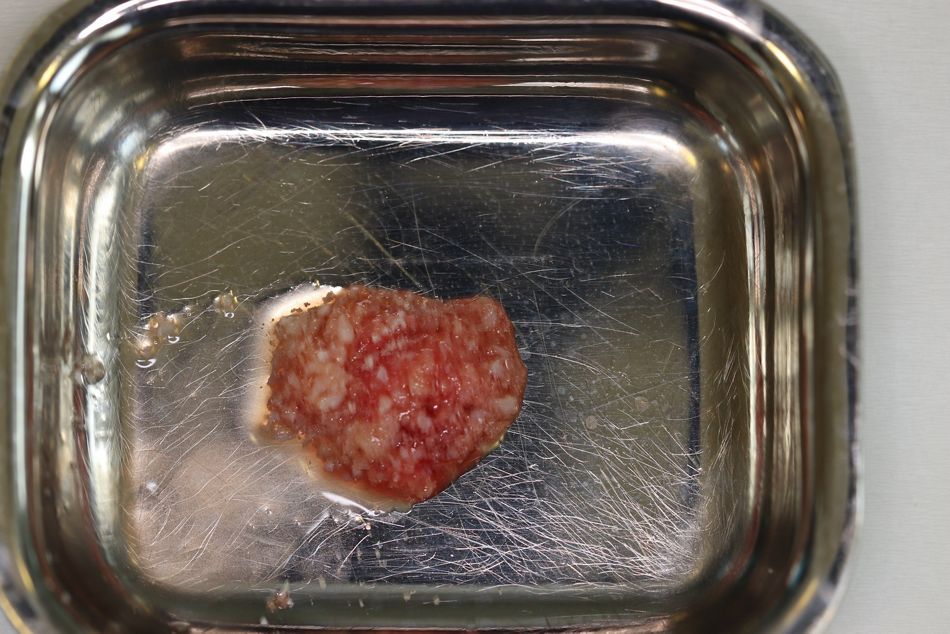

Verwendet wurde im vorliegenden Fall das Implantatsystem Procone (Medentika). Die Aufbereitung des Implantatbettes regio 11 erfolgte nach Bohrprotokoll bis zum Durchmesser 4,3 mm. Der Spalt zum fazialen Knochen wurde mit einem bovinen Augmentat (Cerabone, Straumann) gefüllt. Zur verbesserten Wundheilung sind sowohl das Implantat als auch das Cerabone vor dem Einsetzen mit patienteneigenem Blutplasma bzw. Wachstumsfaktoren (iPRF) benetzt worden (Abb. 7 und 8). Das Implantat wurde nach dem Gewindeschneiden palatinal orientiert inseriert, sodass der Einbringpfosten bukkal hinter der fazialen Fläche der Nachbarzähne platziert war. Der Verschluss erfolgte erstmal mit einer Einheilkappe (Höhe 2 mm) (Abb. 9).